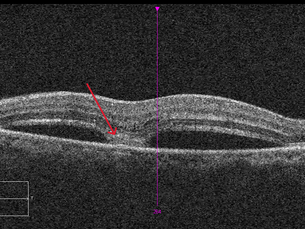

BALAD

Bacillary layer detachment, extensive changes in structure of the retina